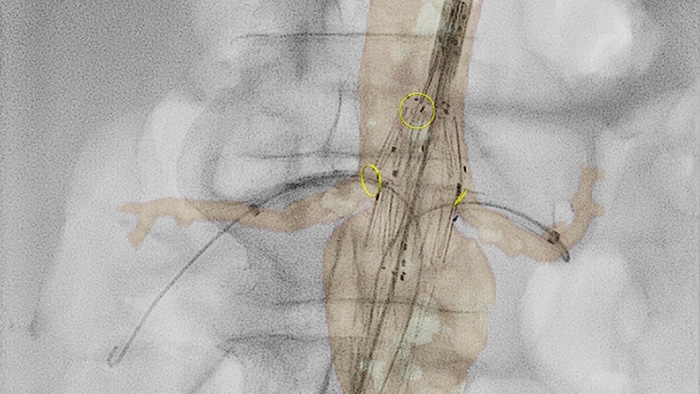

VesselNavigator

VesselNavigator allows reuse of 3D vascular anatomical information from existing CTA and MRA datasets as a 3D roadmap overlay on a live X-ray image. With its excellent visualization, VesselNavigator provides an intuitive and continuous 3D roadmap to guide you through vasculature.